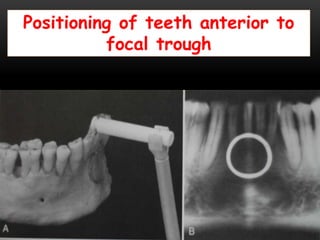

Positioning of teeth anterior to

focal trough

Positioning of teethanterior to focal trough